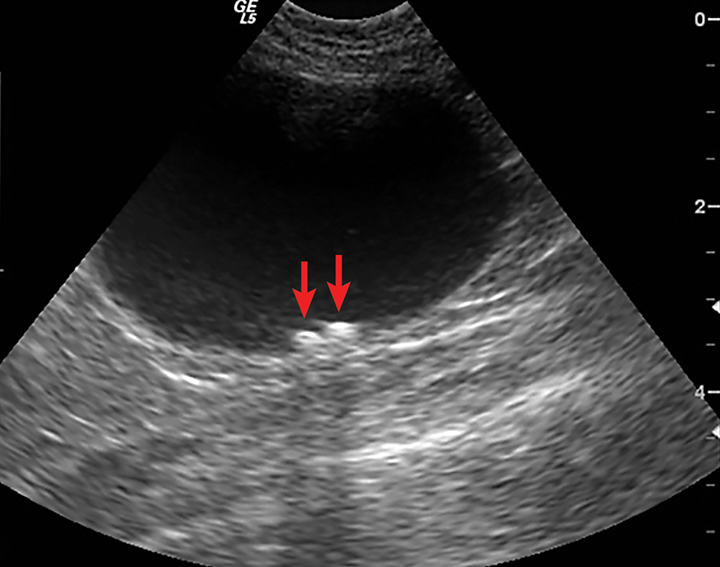

From www.researchgate.net

Ultrasound images of the left (A) and right (B) pancreatic limbs in a Cat Bladder Ultrasound The present study confirms that ultrasonography is an efficient imaging method for examination of lower urinary tract, but radiography and contrast cystography are still. Therefore, do not let your cat urinate within three to six hours of the ultrasound procedure if possible. Always evaluate the trigone area carefully, particularly as it Evaluate the urinary bladder in long and short axes. Cat Bladder Ultrasound.